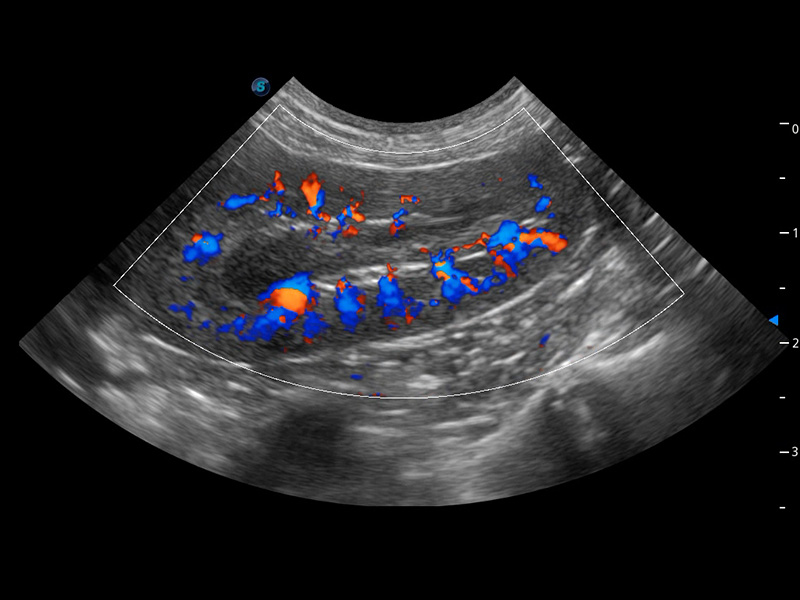

ProPet 60 作為一款高端臺式動物超聲設(shè)備,為動物醫(yī)生的日常診斷提供了一系列貼合動物臨床需求、解決臨床實(shí)際問題的高級成像功能。憑借全系列高清探頭,滿足醫(yī)生對腹部、心臟、生殖、淺表、肌骨等成像的所有需求,切實(shí)幫助您提升檢查效率,提高診斷信心。